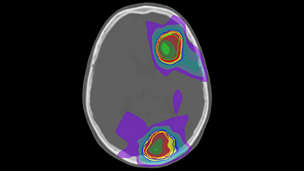

Position with precision

Highly targeted treatment plans rely on MR imaging performed in the treatment position. With MR-RT XD you acquire high quality MR images in the treatment position, boosting accuracy in target delineation and critical structures.